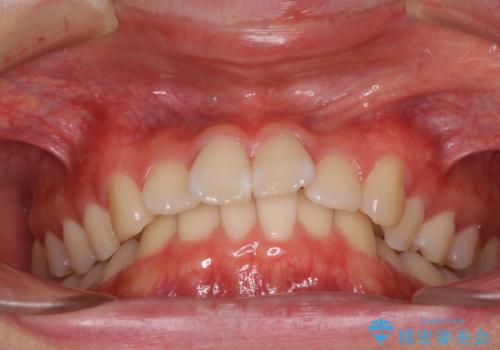

深い咬み合わせとデコボコ ワイヤー矯正で短期治療

- 前歯のデコボコを改善したいとのことで来院された患者様です。

結果として、1年かからずに奥歯の咬み合わせを改善することができました。